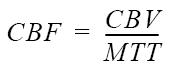

| Equation | BrainStat AIF | BrainStat |

|---|---|---|

| CBV |  |  |

| CBF |  |  |

| MTT |  |  |

| table legend | p = density of brain tissue R(t) = Residue function kH = correction factor | |